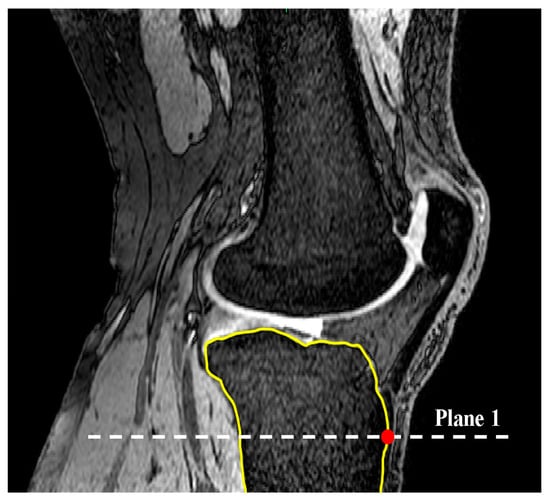

2.1. Medial and Lateral Tibial Slope Measurement Methodology

2.2. Coronal Tibial Slope Measurement Method